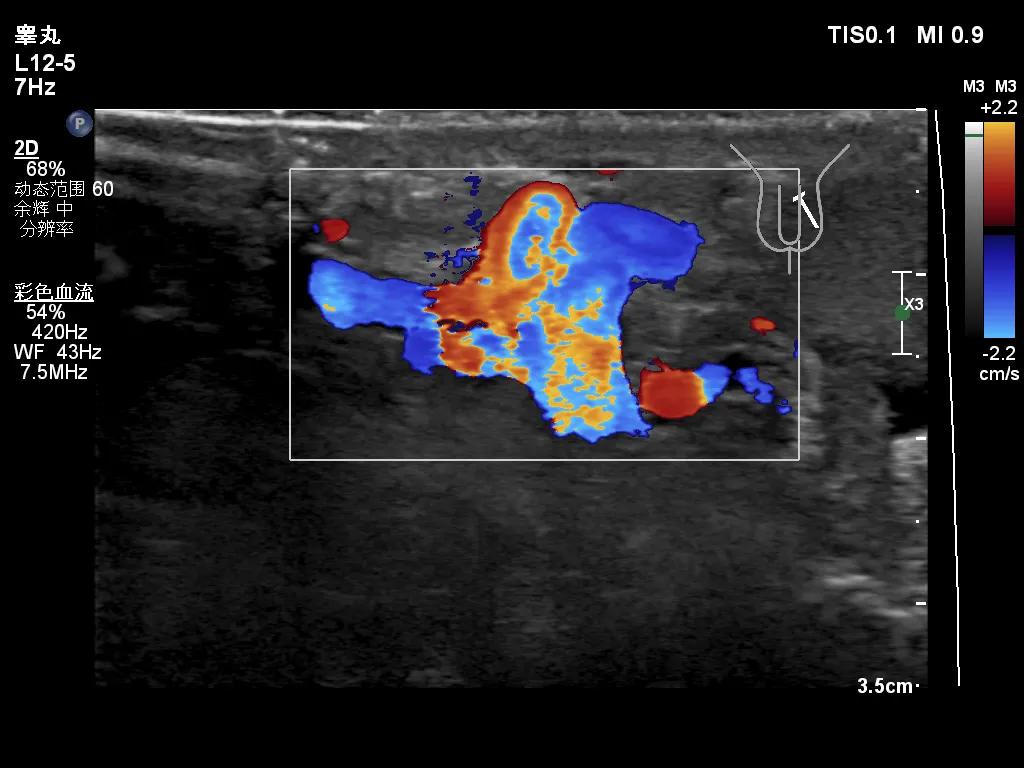

其实我们最关心的是,怎么就可以诊断为精索静脉曲张了,有什么标准,这就需要联合我们的超声检查一起解释了,目前诊断精索静脉曲张需要满足两个条件,1. 精索静脉曲张扩张,内径超过2.0mm;2.乏式实验(其实就是增加腹压的动作),精索静脉内可见大量返流信号(正常情况下,精索静脉瓣膜功能是良好的,乏氏试验后会导致瓣膜关闭,从而阻滞血液返流)。

乏式试验下,大量的返流信号